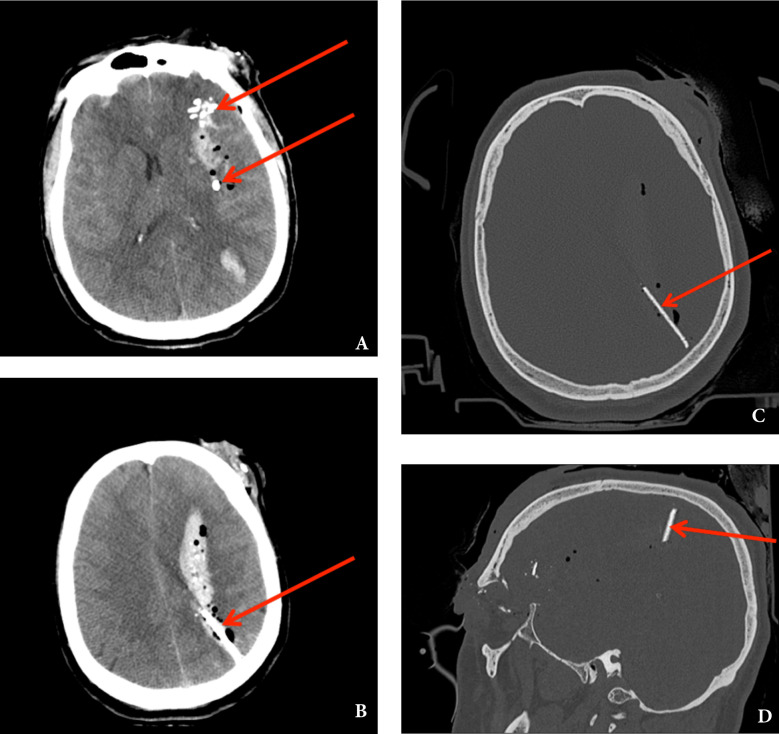

紧急头部CT显示在左眼眶外侧和左外直肌(可能是入口伤口)中有多个骨碎片和金属异物(图2 a),以及左眼眶的上方和后方有被压碎的眼球(图2 b)。颅内可见造成脑实质创伤性损伤的投射物路径,充满含气小气泡并被蛛网膜下腔出血包围(图2 b)。它还显示了贯穿整个脑实质的充满血液的穿透伤口撞击通道,从左侧颞底区域向上蔓延到左侧顶叶,其中充满了残留的异物/骨碎片和少量空气(图3 a)。一个尖锐的金属物体卡在左顶叶皮质下,垂直于顶骨(图3 b、c和d)。计算机断层血管造影(CTA)显示脑血管没有明显的血管损伤,但由于金属伪影,成像受到限制。

图2、急诊头颅计算机断层扫描(CT)显示蛛网膜下腔出血,左侧眼眶外侧眼外肌和左侧直肌中有放射性密集的多发性骨碎片和金属异物(a),以及左侧眼眶中上方和后方有被破坏的眼球的(箭头),以及充满少量空气的沿着抛射路径进入颅内的气肿变化(气颅) (箭头)(b)

图3、原发性轴位脑CT显示脑水肿,显示沿贯穿伤撞击管(箭头)颅内残留多个放射性高密度异物和骨碎片,充满脑出血和少量颅内空气(a)。贯穿脑实质的充满血液的伤口通道,终止于左侧顶叶皮质下,尖锐的金属物体卡在此处(箭头)(b)。轴位(c)和矢状位脑CT骨窗重建(d),识别垂直于顶骨的颅内残留金属物体(箭头)